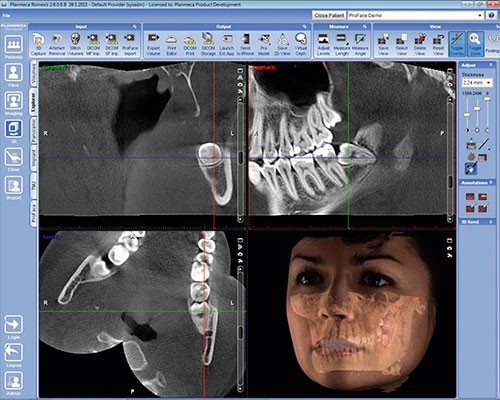

Exclusivo Sistema de Fotografía 3D disponible para todos nuestros clientes. IDM y Planmeca son pioneros en introducir este tipo de concepto en el Perú y consiste en la adquisición de una fotografía 3D sin necesidad de emitir radiación.